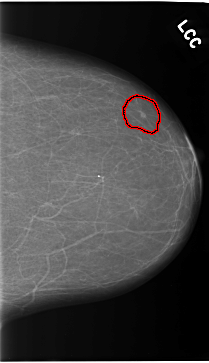

C_0119_1.LEFT_CC

FILE: C_0119_1.LEFT_CC.OVERLAY

TOTAL_ABNORMALITIES 1

ABNORMALITY 1

LESION_TYPE MASS SHAPE OVAL MARGINS CIRCUMSCRIBED

ASSESSMENT 4

SUBTLETY 3

PATHOLOGY MALIGNANT

TOTAL_OUTLINES 1

BOUNDARY